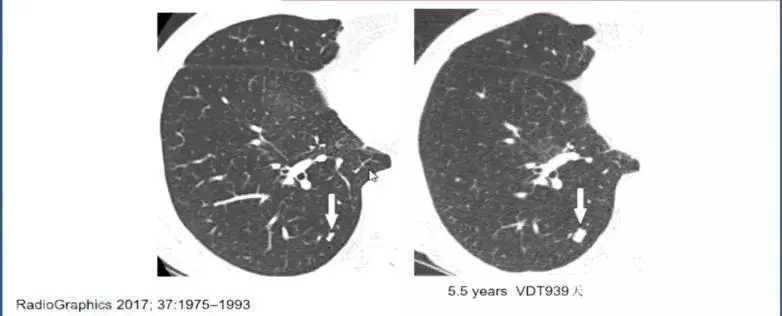

需要注意的是,并非所有的良性肺结节都不会生长,错构瘤会缓慢地生长。

图2 错构瘤五年生长对比图